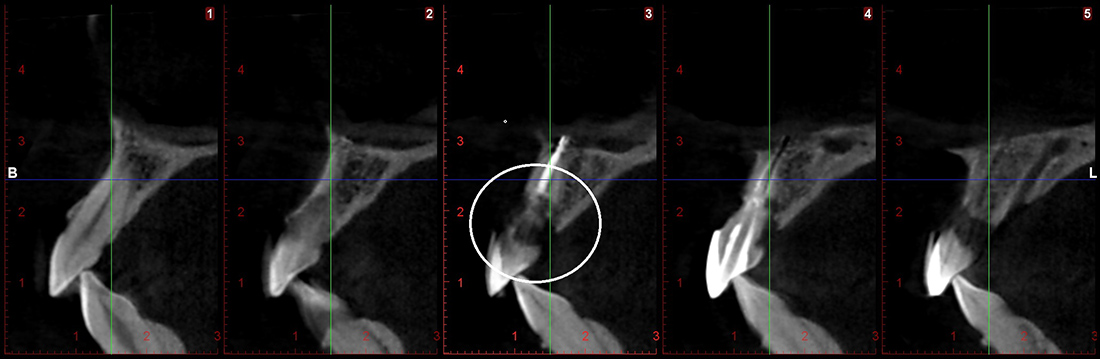

Пациентка П., 26 лет. Обратилась с жалобами на подвижность и боли в области верхнего центрального резца. При клиническом и рентгенографическом обследовании выявлена внутриканальная резорбция корня, поперечный перелом и разрушение наружной костной стенки.

Под местной анестезией был удален зуб, установлен имплант, проведена пластика мягких тканей и фиксирована временная коронка. Через три месяца проведена оценка импланта, и мы перешли к замене временной коронки на постоянную. Опорой для коронки на импланте послужил индивидуальный циркониевый абатмен.